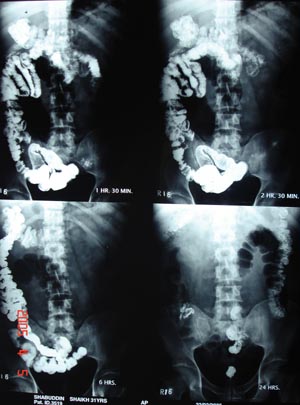

View Barium meal with follow through

Barium meal with follow through

Films at various interval.